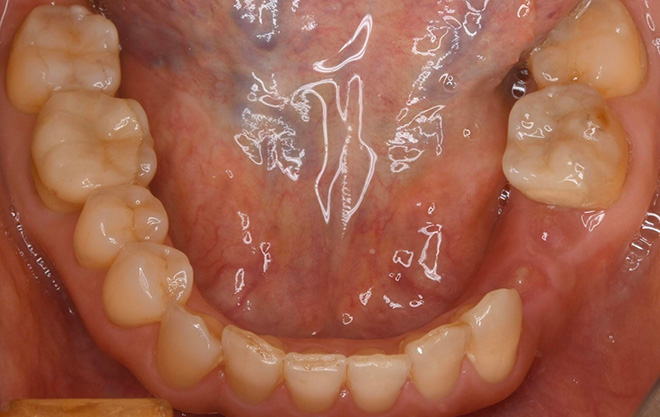

戸丸先生が製作したインプラント上部構造(セラミック歯)の治療例

治療前の口腔内写真

治療後のレントゲン写真

治療後の口腔内写真

患者様は40代女性、治療期間は4ヶ月。

この症例の治療費

奥歯スタンダードインプラント2本→1本あたり440,000円(税込)

総額880,000円(税込)

この症例のリスク

インプラントが稀に脱落することがあります。

その場合は10年保証が付いていますので、速やかに無料対応をさせて頂きます。